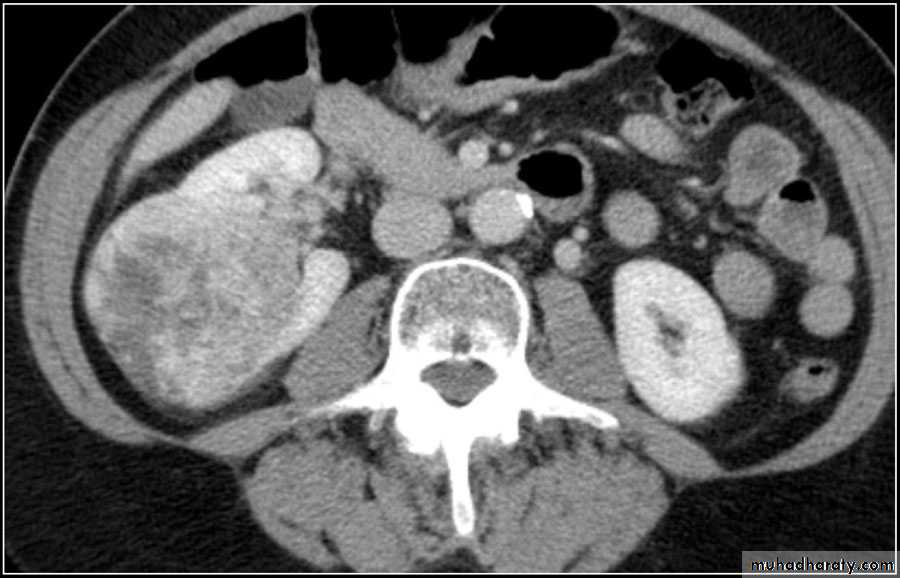

• Tumors

• Renal cell carcinoma:• Comprise 85% of renal malignancy

• Features

• 1. Soft tissue mass on KUB.

• 2. Irregular filling defect with destruction of calyces on IVU.

• Heterogeneous necrotic mass on CT scan may extend to the perinephric area, renal vessels with regional LN and distant metastasis to the lungs or bone.